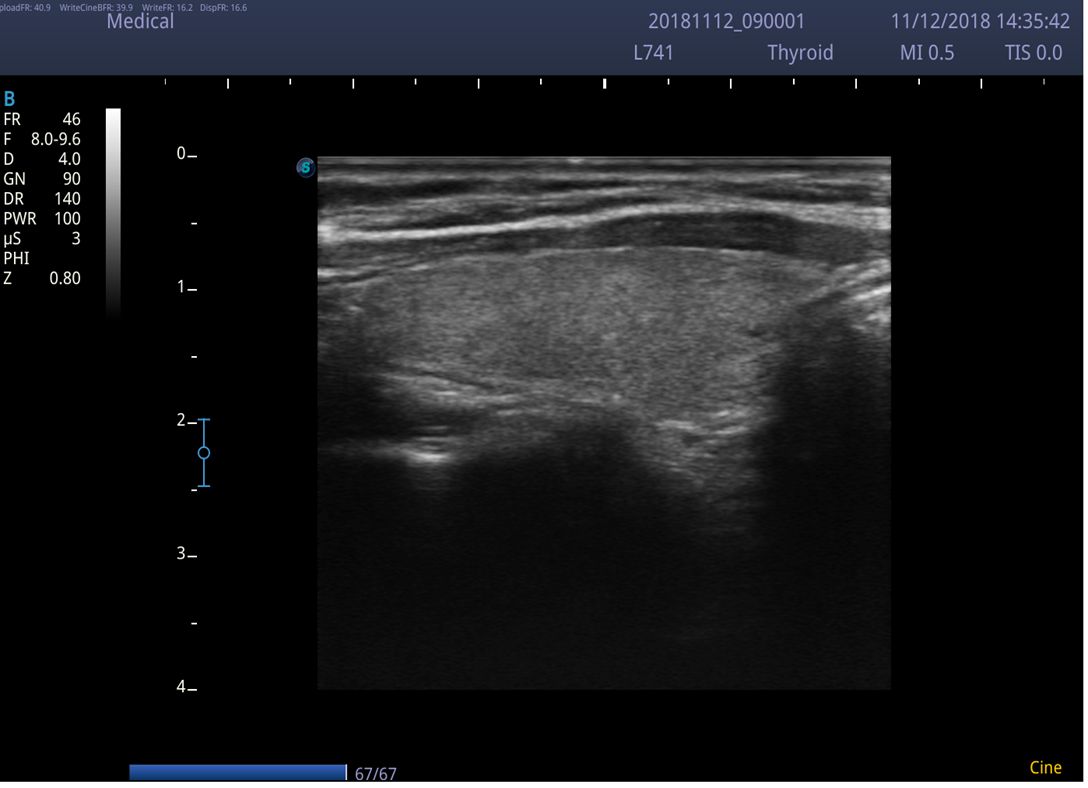

Chất lượng hình ảnh 2D trên máy siêu âm chuyên tim SonoScape P9:

Công nghệ Sono-help (Built-in Scanning Tutorials): Hướng dẫn quét siêu âm tích hợp sẵn, giúp bạn nâng cao kỹ năng quét và chẩn đoán. Sono-Help là một hướng dẫn đầy cảm hứng hiển thị vị trí đầu dò, minh họa giải phẫu và các ví dụ hình ảnh siêu âm tiêu chuẩn. Là một tài liệu tham khảo hữu ích mà các bác sĩ lâm sàng ít kinh nghiệm có thể dựa vào, Sono-Help bao gồm nhiều ứng dụng bao gồm gan, thận, tim, vú, tuyến giáp, sản khoa, mạch máu, v.v.